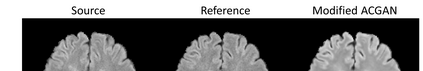

Multiple Sclerosis (MS) is a chronic progressive neurological disease characterized by the development of lesions in the white matter of the brain. T2-fluid-attenuated inversion recovery (FLAIR) brain magnetic resonance imaging (MRI) provides superior visualization and characterization of MS lesions, relative to other MRI modalities. Longitudinal brain FLAIR MRI in MS, involving repetitively imaging a patient over time, provides helpful information for clinicians towards monitoring disease progression. Predicting future whole brain MRI examinations with variable time lag has only been attempted in limited applications, such as healthy aging and structural degeneration in Alzheimer's Disease. In this article, we present novel modifications to deep learning architectures for MS FLAIR image synthesis, in order to support prediction of longitudinal images in a flexible continuous way. This is achieved with learned transposed convolutions, which support modelling time as a spatially distributed array with variable temporal properties at different spatial locations. Thus, this approach can theoretically model spatially-specific time-dependent brain development, supporting the modelling of more rapid growth at appropriate physical locations, such as the site of an MS brain lesion. This approach also supports the clinician user to define how far into the future a predicted examination should target. Accurate prediction of future rounds of imaging can inform clinicians of potentially poor patient outcomes, which may be able to contribute to earlier treatment and better prognoses. Four distinct deep learning architectures have been developed. The ISBI2015 longitudinal MS dataset was used to validate and compare our proposed approaches. Results demonstrate that a modified ACGAN achieves the best performance and reduces variability in model accuracy.